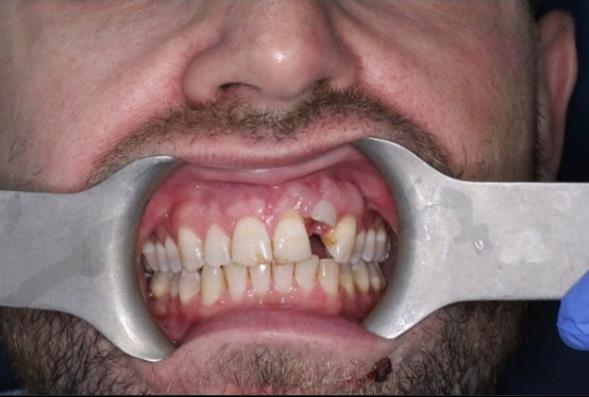

Dental trauma management

Pre-operative photo and X-ray

6 month review